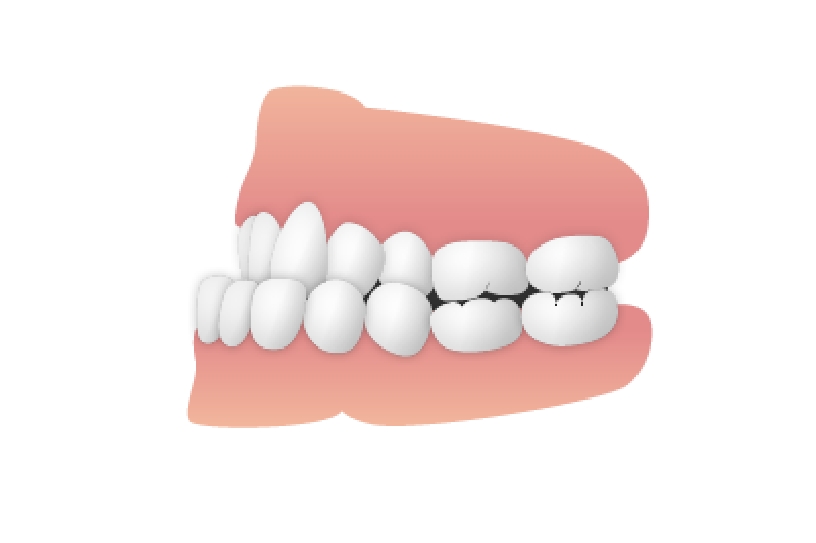

上顎前突(じょうがくぜんとつ)

上顎前突

上顎の前歯が正常な位置より前に出ている症例で、いわゆる「出っ歯」のケースです。原因はさまざまに考えられますが、最も大きなものは、舌の使い方にあると思われます。舌は物を飲み込むとき、上側に動くのが普通です。ところが、一部の人は前に出るため、この力で歯を押し出してしまうのです。 舌の前後動が定常化すると、鼻の気管を圧迫し、口呼吸の原因となる場合があります。そこで、治療を行うのと同時に、ガムトレーニングで舌の癖を治していく必要があるでしょう。いわゆる「矯正治療の後戻り」が起きる理由のひとつに、この癖が抜けきっていないことなどが考えられます。

上顎前突 治療後

主訴 前歯が出ているのが気になる口が閉じにくい

診断名あるいは主な症状 上顎前突

年齢 11歳4ヶ月

治療に用いた主な装置 ブラケット装置 スタンダードエッジワイズ法

抜歯部位 上下両側第一小臼歯

治療期間 2年11ヶ月

治療費概算 70万+月々の調整料

リスク副作用 歯の根が吸収して短くなる場合があります。

歯茎が痩せて下がる場合があります。

舌で歯を押す唇を噛む等の癖が改善されない場合は、治療期間が長引く場合があります。

定期的に通院できない、キャンセルが多い場合は治療期間が長引きます。